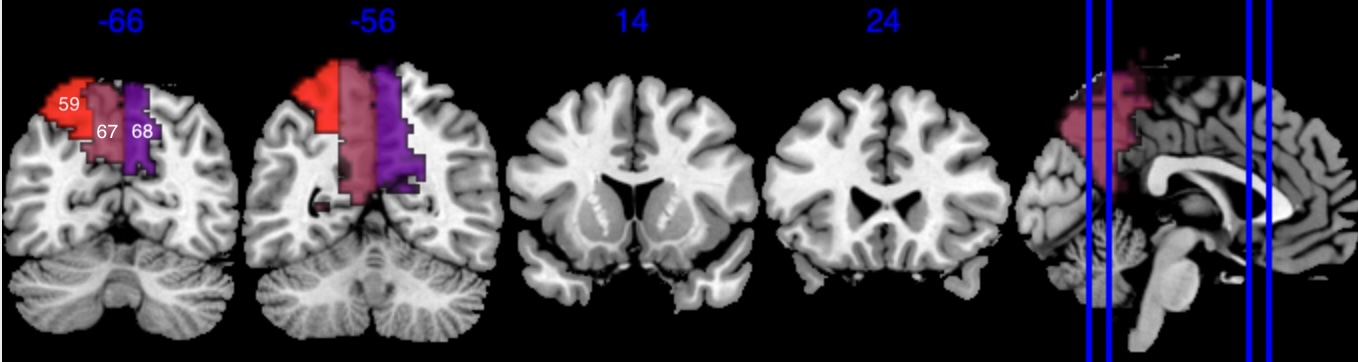

We performed 100,000 iterations for the outcome model (1), discarding the first 50% as burn-in and thinning to retain 1,000 posterior samples. For the mediator model (2), we ran 40,000 iterations with a 30,000 burn-in, thinning every 10 iterations to obtain 1,000 posterior samples. Table 3 gives a summary of both the overall NIE and NDE and the top seven regions identified with the largest number of active voxels. The definition of NIE in each region is , where is the collection of all voxels in region . The rule for selecting the active voxels is based on cutting the posterior inclusion probability (PIP) at 50%, and the three regions with active voxels are reported in Table 3. Due to the very small effect sizes and low signal-to-noise ratio, we also include regions with voxels’ PIP greater than 10%. The posterior of NDE has a mean of 0.27 with the 95% credible interval . The posterior of NIE has a mean of 0.0885 with the 95% credible interval . The total effect of parental education level on general cognitive ability score is 0.36, with 95% credible interval (0.29,0.45). This suggests that parents with college degrees have a positive impact on children’s cognitive abilities, and about 25% of the effect is mediated through brain cognitive development. Figure 5 shows the estimated activation regions and the NIE in coronal view slides. Among the top identified activation regions, the most interesting is the left precuneus, which plays a key role in episodic memory, visuospatial processing, and self-consciousness (lou2004parietal; wallentin2006parallel). This region has been consistently implicated in cognitive processes related to memory retrieval and spatial awareness, which are crucial components of children’s cognitive development. In addition, other identified regions, such as the left inferior parietal region and the left postcentral gyrus, are associated with the interpretation of sensory information (radua2010neural; diguiseppi2023neuroanatomy). These regions are involved in integrating and processing sensory inputs, which are essential for tasks that require coordination between perception and cognition, such as working memory and executive function. These findings align with existing literature on the neural correlates of cognitive function, particularly in children. By identifying regions that have been consistently associated with cognitive processes, our results not only demonstrate the scientific validity of the BIMA approach but also provide meaningful insights into the brain areas that underlie cognitive abilities as captured by the ABCD study.

| Posterior inclusion probability (color range ) |

![]() |

| Positive posterior mean of the spatial mediation effects (color range ) |

| Negative posterior mean of the spatial mediation effects (color range ) |